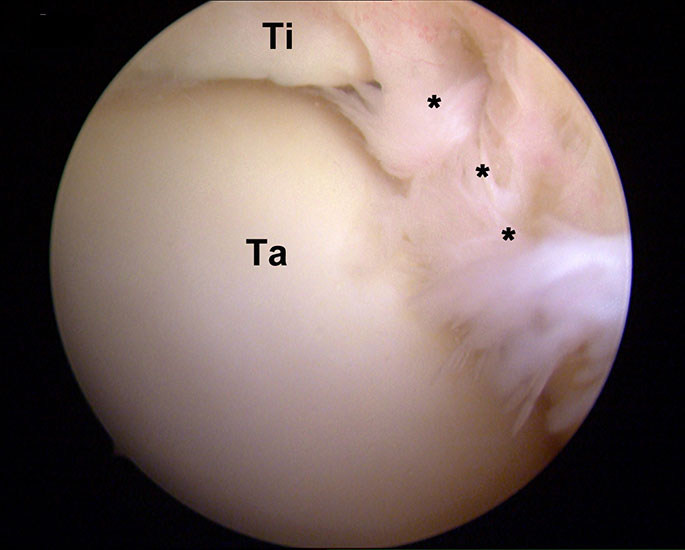

Abbildung 8, Video 3

Hypertrophie der Synovia und der Gelenkkapsel (*) im anterolateralen Kompartiment am linken OSG. Das Gewebe rutscht bei Bewegungen und unter Belastung in den Gelenkspalt zwischen Tibia (Ti) und Talus (Ta) und verursacht schmerzhafte Einklemmungen. Es erfolgt eine Resektion mit einer bipolaren Radiofrequenzsonde über das anterolaterale Standardportal. Auf einen ausreichenden Abstand der Radiofrequenzsonde zur Knorpeloberfläche ist zu achten, um iatrogene Hitzeschäden zu vermeiden. Hilfreich ist eine Arbeitsrichtung vom Talushals ausgehend nach kraniolateral. Durch maximale Dorsiflexion des Fußes weitet sich das ventrale Kompartiment und das Gewebe ist weniger gespannt. Hierdurch vergrößert sich der Arbeitsraum und wird die Resektion vereinfacht. Darüber hinaus wird die Knorpeloberfläche des Talus von der Tibia bedeckt und geschützt.